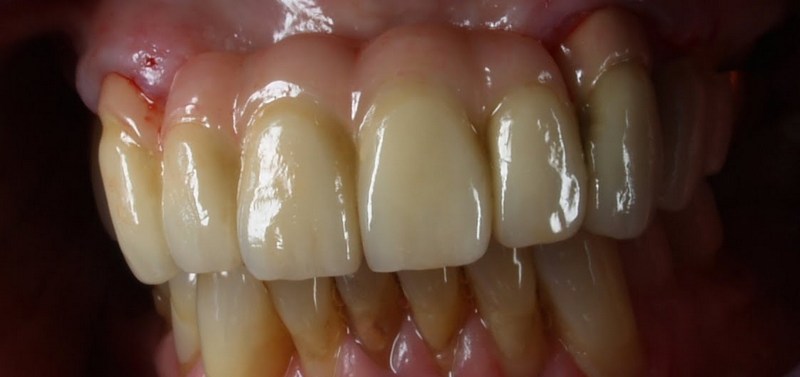

Meisterarbeit von Peter Dengel

Vom Langzeitprovisorium zur TEK 1 Arbeit